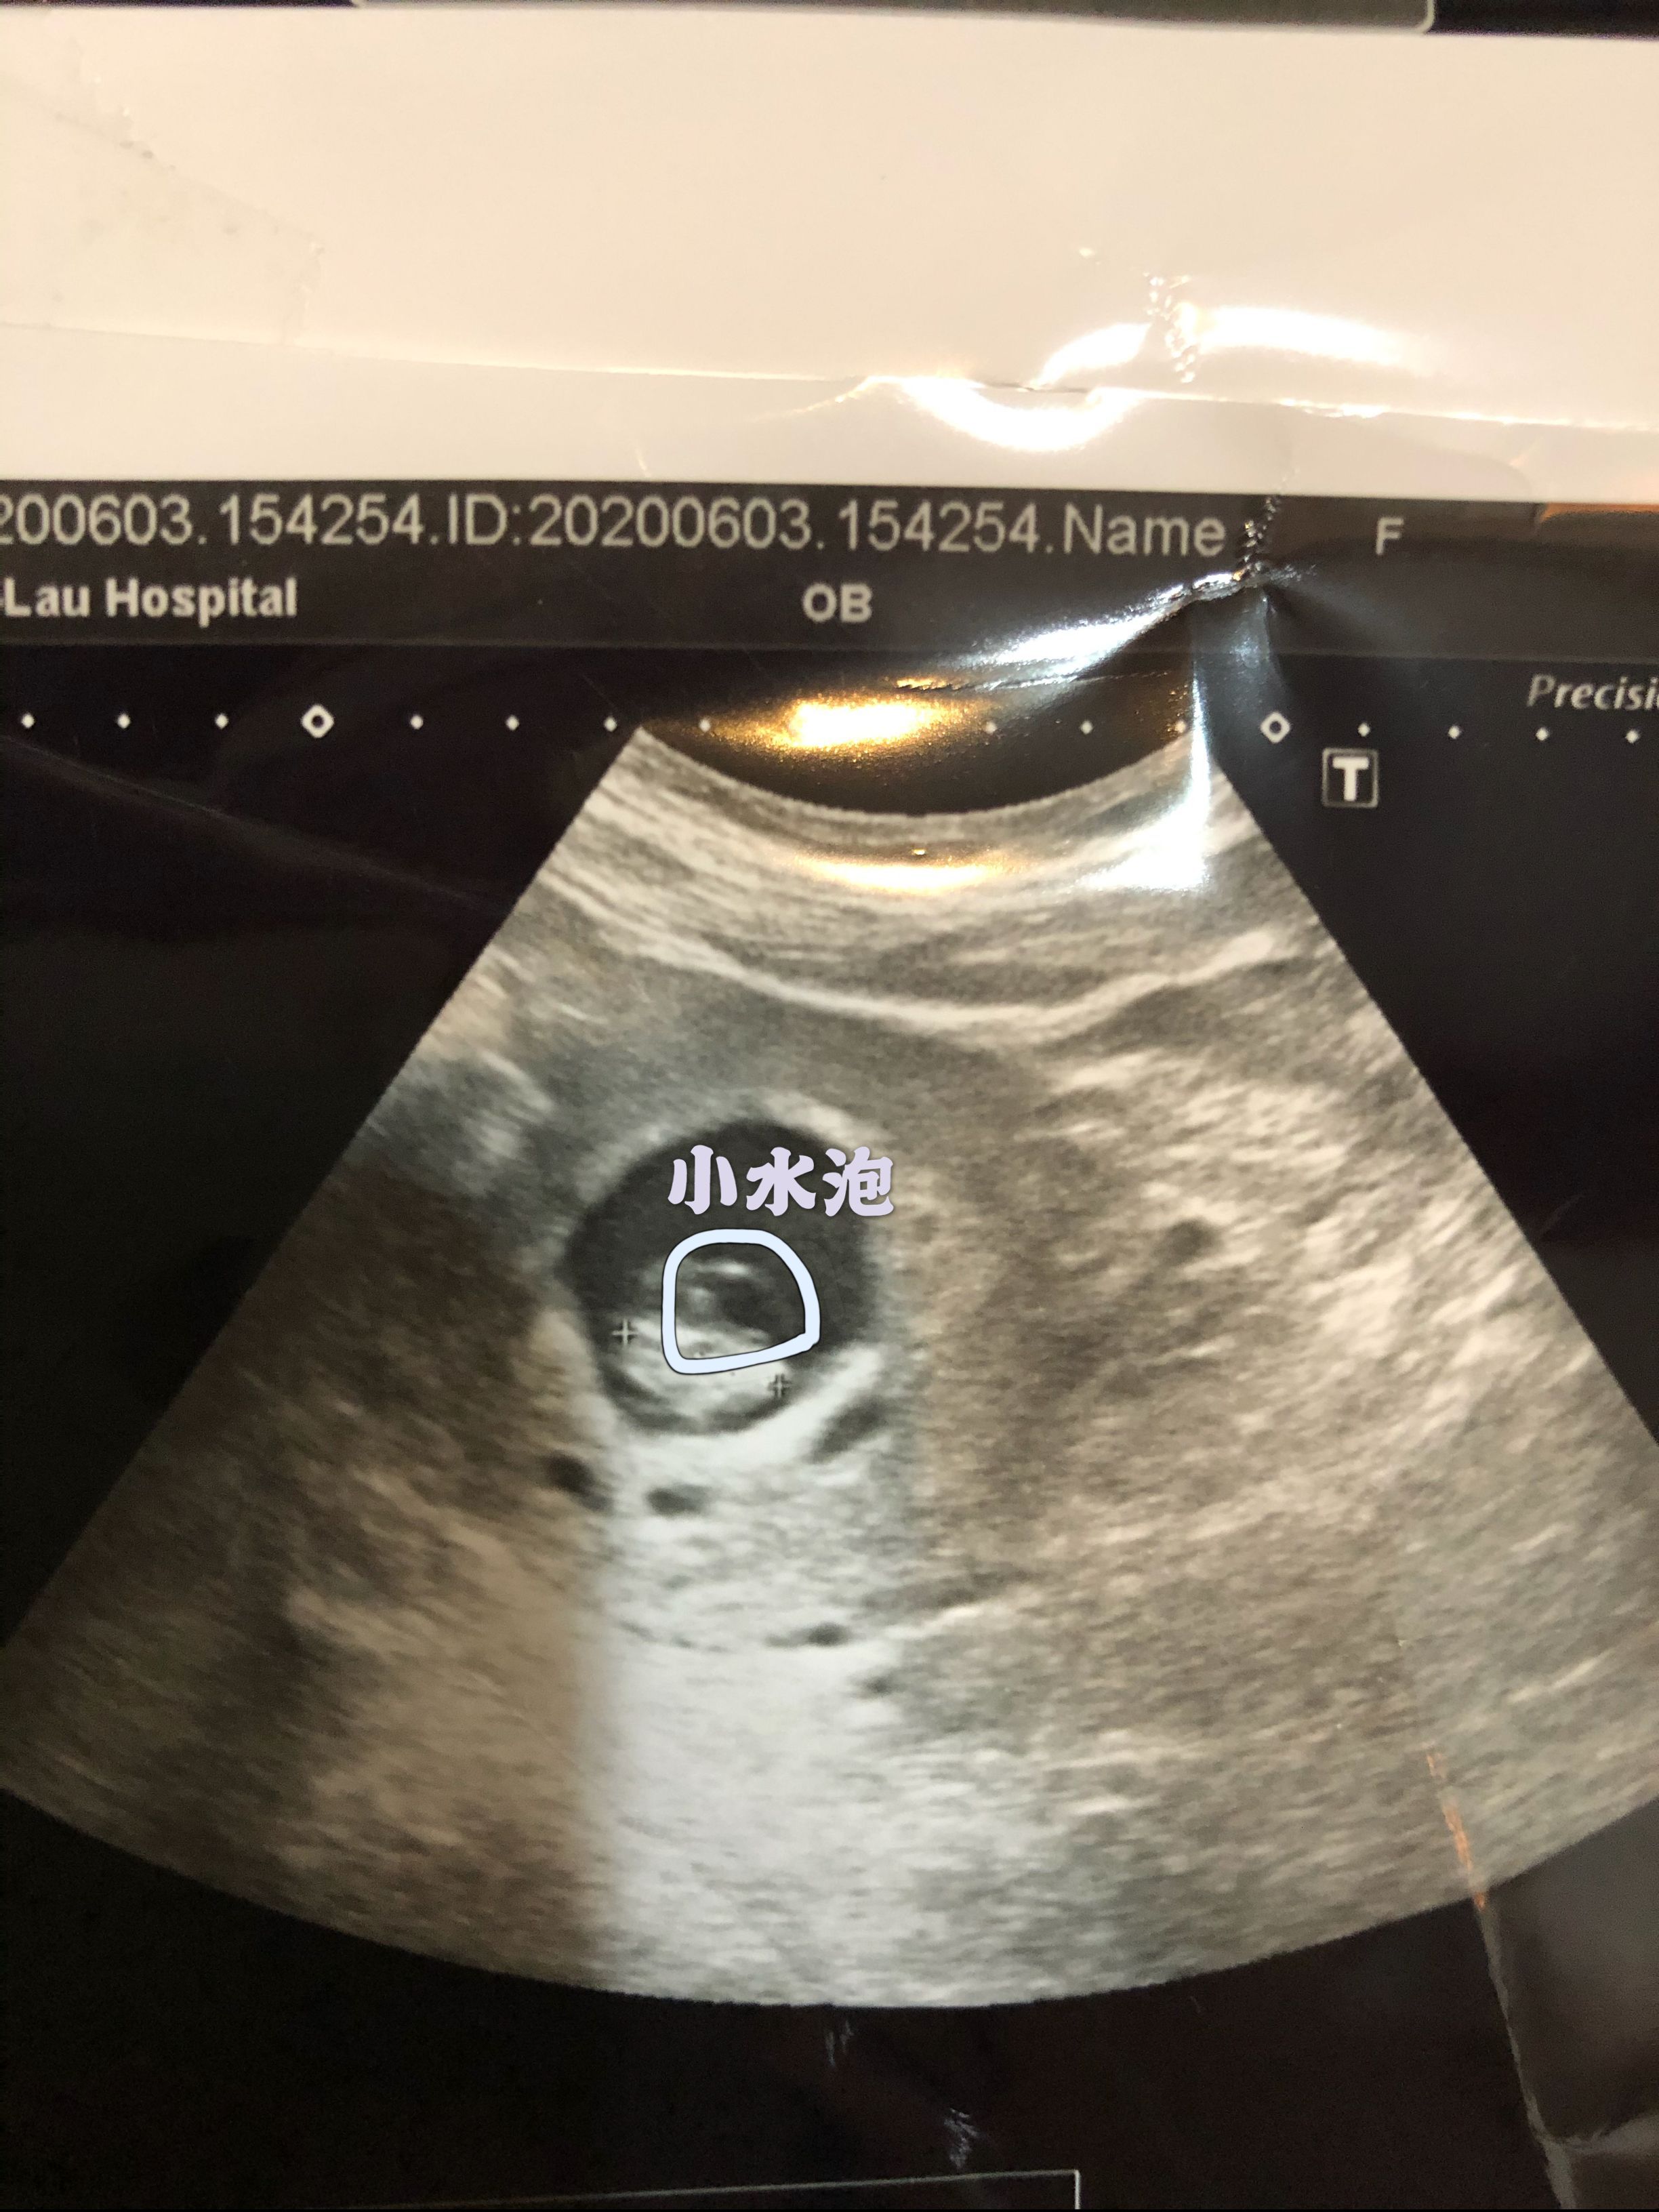

胚囊裡面被照有小水泡

今天去回診,照超音波,醫生說大概8週,有心跳,但卻發現胚囊裡面有小水泡,醫生只說有點奇怪,怎麼小孩的上方長小水泡,然後就說兩個禮拜後再來看看。 後來我問醫生胚囊長水泡,是什麼意思,他一樣回答,兩個禮拜在來看看。 其實心裡就是很擔心,但醫生的這樣的回答,我也不知道該怎麼辦。

有其他媽媽們遇到這樣的問題嗎? 想到擔心兩個禮拜,簡直是煎熬。有點難過。